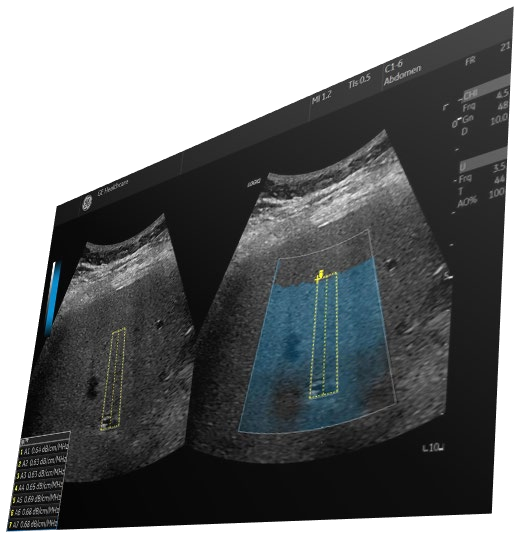

Στο Διαγνωστικό Κέντρο Ηρόδοτος εφαρμόζουμε την πρωτοποριακή  υπερηχογραφική τεχνική UGAP, (Ultrasound-Guided Attenuation Parameter), μία καινοτόμο, αναίμακτη μέθοδο υπερήχου (στην ουσία πρόκειται για υπερηχογραφημα κοιλίας)  που όμως  επιτρέπει την αντικειμενική και ποσοτική εκτίμηση της λιπώδους διήθησης του ήπατος, μετρώντας με ακρίβεια το λίπος στο ήπαρ και κατατάσσει τη λιπώδη διήθηση σε στάδια S1, S2 και S3.»

UGAP (Ultrasound-Guided Attenuation Parameter)

Τι αλλάζει με τη μέθοδο UGAP;

Μέχρι πρόσφατα, η εκτίμηση του λιπώδους ήπατος βασιζόταν κυρίως σε υποκειμενική υπερηχογραφική εικόνα ή σε επεμβατική βιοψία.

*Η μέθοδος UGAP η  «ηλεκτρονική βιοψία» χωρίς νυστέρι:

*Μετρά με ακρίβεια πόσο λίπος υπάρχει στο ήπαρ. Δηλαδή όταν εκτελείται ο συγκεκριμένος υπέρηχος, το μηχάνημα στέλνει ηχητικά κύματα μέσα στο σώμα. Όσο περισσότερο λίπος υπάρχει, τόσο περισσότερο «εξασθενεί» το κύμα. Η καινοτόμος μέθοδος μετρά ποσοτικά πόσο «εξασθενεί» το υπερηχογραφικό κύμα όταν περνά μέσα από το ήπαρ και με βάση αυτή τη μέτρηση, η στεάτωση κατατάσσεται σε τρία στάδια (ήπια, μέτρια, σοβαρή), επιτρέποντας αξιόπιστη παρακολούθηση στο χρόνο (S1, S2, S3).

*Υπάρχει υψηλή επαναληψιμότητα και αξιοπιστία των μετρήσεων

*Η εξέταση είναι απλή, γρήγορη και ανώδυνη

*Δεν απαιτείται καμία επεμβατική διαδικασία

*Η μέθοδος προσφέρει ακριβή απεικονιστική πληροφορία χωρίς τους κινδύνους της παραδοσιακής βιοψίας.